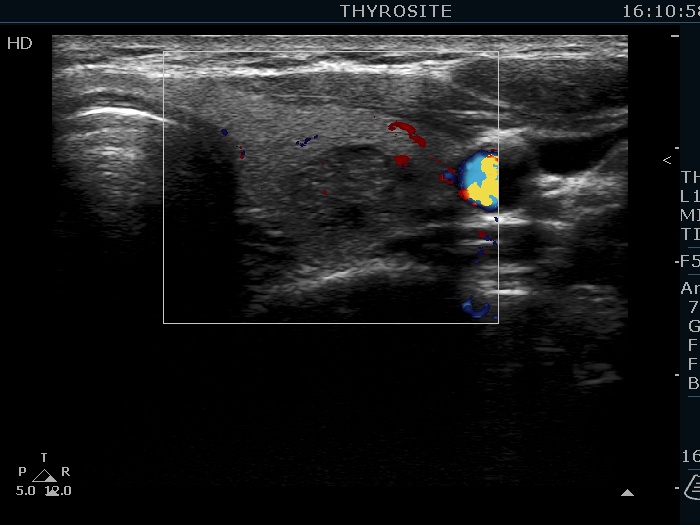

Middle part of the left lobe, transverse scan, microflow imaging. The lesions are avascular.